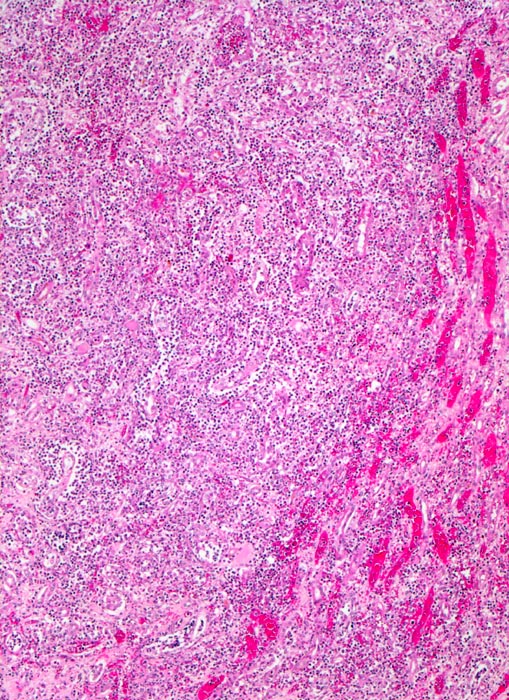

Destruktives streifenförmiges granulozytäres Infiltrat. Die Tubuli sind nicht mehr erkennbar. Am Rand des Infiltrates hyperämische Gefässe (makroskopisch gelber Herd mit rotem Randsaum).